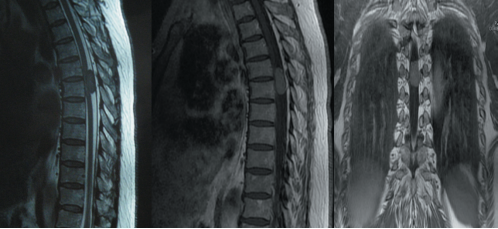

通常由椎管外恶性肿瘤(如前列腺癌、膀胱癌或肺癌等)(图4)侵入椎管内所引起的,这类情况约占椎管内肿瘤总数的四分之一。

图4.胸段椎管内转移瘤MRI图像